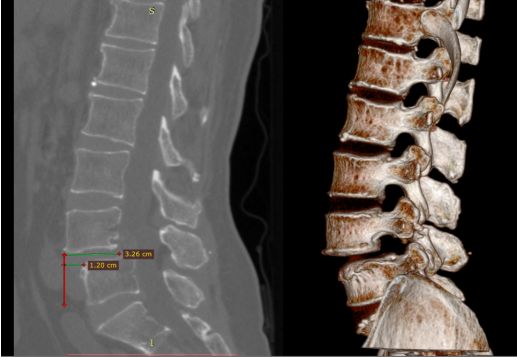

术前CT

术前CT提示腰4椎体向前滑脱,幅度超过椎体横径1/3,为II度滑脱。